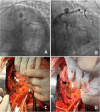

Coronary artery aneurysms (CAAs) are uncommon and describe a localized dilatation of a coronary artery segment more than 1.5-fold compared with adjacent normal segments. The incidence of CAAs varies from 0.3 to 5.3%. Ever since the dawn of the interventional era, CAAs have been increasingly diagnosed on coronary angiography. Causative factors include atherosclerosis, Takayasu arteritis, congenital disorders, Kawasaki disease (KD), and percutaneous coronary intervention. The natural history of CAAs remains unclear; however, several recent studies have postulated the underlying molecular mechanisms of CAAs, and genome-wide association studies have revealed several genetic predispositions to CAA. Controversies persist regarding the management of CAAs, and emerging findings support the importance of an early diagnosis in patients predisposed to CAAs, such as in children with KD. This review aims to summarize the present knowledge of CAAs and collate the recent advances regarding the epidemiology, etiology, pathophysiology, diagnosis, and treatment of this disease.